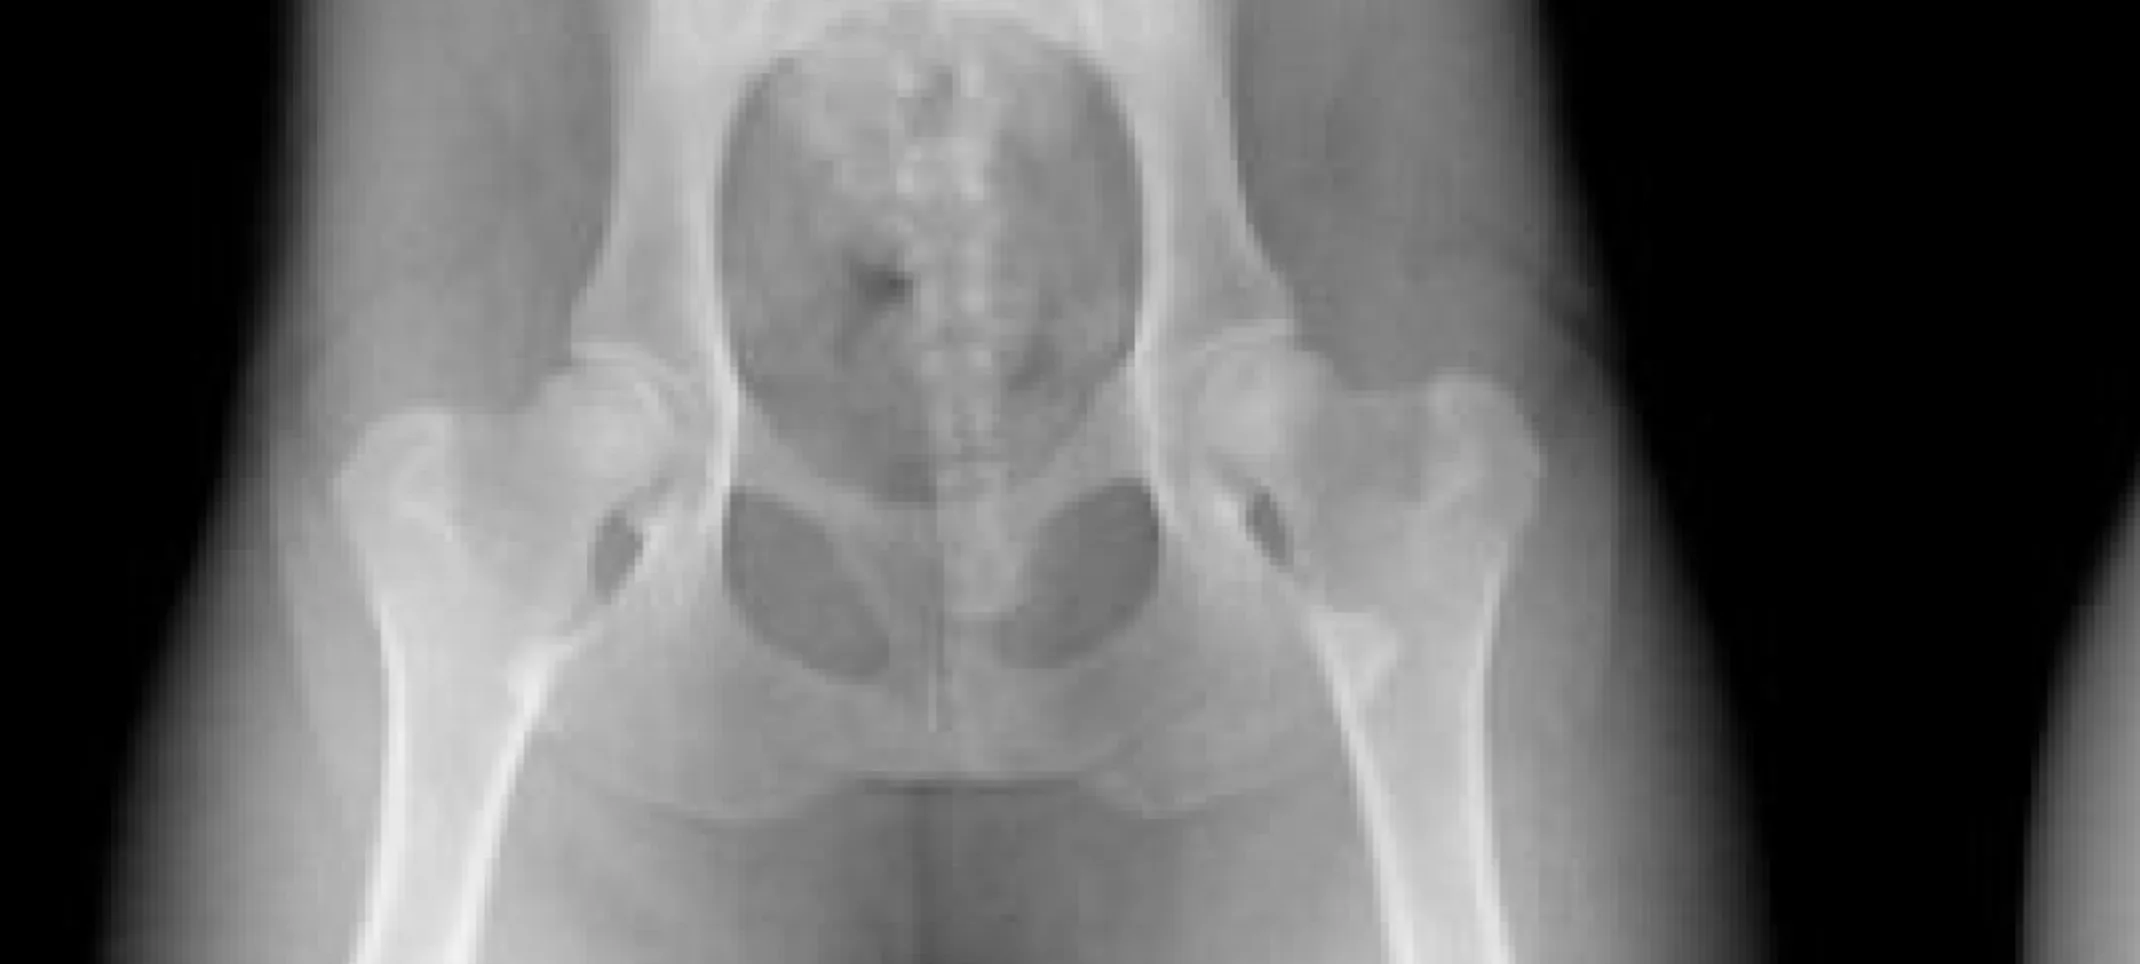

Below is an example of the positioning required for radiographic evaluation for hip dysplasia.

Radiographs of hips, elbows, knees and shoulders can be submitted . There is a standard by which all veterinarians must follow regarding the positioning of the animal being radiographed, the labeling of the radiographs and forms submitted. In this way, the x-rays are consistent. The Orthopedic Foundation of Animals keeps a database of all breeds over many generations. When dogs are radiographed, owners need to bring in their AKC registration forms and their pet should be micro chipped for identification.